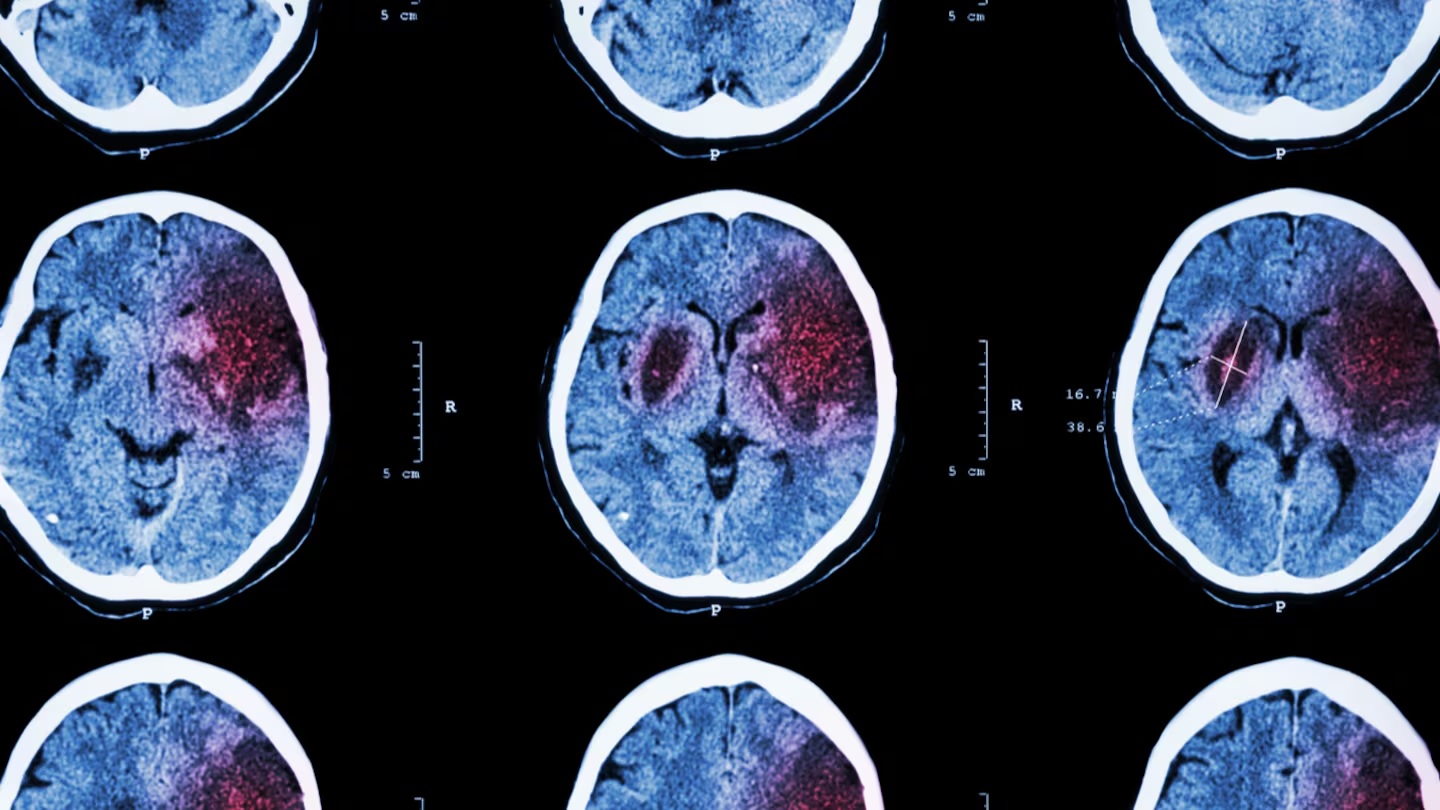

El Accidente Cerebrovascular (ACV), también conocido como ictus o stroke, es una de las principales causas de discapacidad y mortalidad en el mundo. Se produce cuando el flujo sanguíneo hacia una parte del cerebro se interrumpe, lo que puede provocar daños irreversibles en cuestión de minutos.

. El isquémico, que ocurre cuando un coágulo bloquea una arteria cerebral e impide que la sangre llegue al tejido.

. El hemorrágico, que se produce cuando un vaso se rompe y provoca una hemorragia dentro del cerebro.